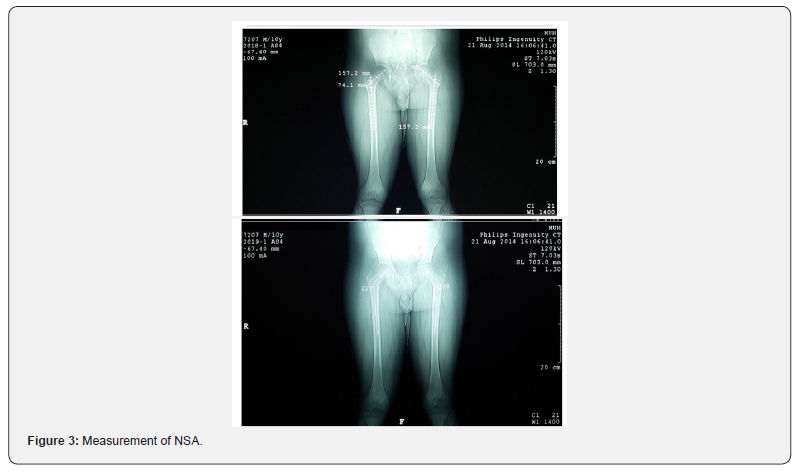

Measurement of Neck-shaft Angle

The NSA is the angle formed by the intersection of the femoral neck and shaft axes (Figure 3).

A. Computing the shaft Axis

Horizontal lines in three sequential points 1 Cm apart at the isthmus were drawn from one side of the shaft to the opposite side, and then the mid points of these lines were connected to from the shaft axis.

B. Computing the Neck Axis The axis of the neck was drawn from the center of the head of the femur towards midpoint of the base of the neck.